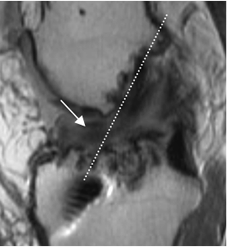

Fig 143 A. Pinzamiento del injerto.

A: RM sagital en DP. Injerto con alteración de su señal. Su parte distal se ubica por delante de la línea intercondílea, por pinzamiento.

Fig 143 B. Pinzamiento del injerto.

A: Rx lateral y B: RM sagital en T1. Túnel tibial de localización anterior, (Flechas), lo que predispone al pinzamiento. Adicionalmente el tornillo del túnel femoral está muy horizontalizado.

C: RM sagital en T2. Injerto por delante de la línea de Blummensaat, signo de pinzamiento. Existe alteración en la señal y solución de continuidad de la mayoría de sus fibras en el tercio medio, por ruptura parcial. (Flecha gruesa).